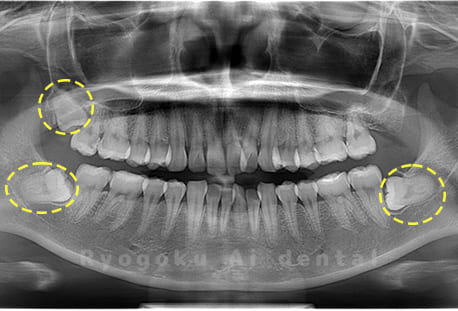

Case03

- 原因

- 上顎、下顎の親知らず

- 治療内容

- 上下4本の親知らずを抜歯したケースです。

<リスク・副作用>

手術後は痛み、腫れ、痺れなどの副作用が生じる場合があります。